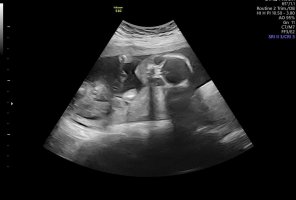

Det beste for å se kjønn nå er et pottyshot, altså et bilde fra rumpa og opp med beina stikkende ut. Hvis jordmor sa gutt så tror jeg dessverre sannsynligheten er ganske stor for at hun har rett. Skjønner du vil ha jente etter så mange gutter, men sannsynligheten øker også litt for å få det samme kjønnet man har om man har flere. Du kan jo ta familien Ingebrigtsen (løpe familien) som et eksempel, de fikk vel 5 gutter før de fikk en jente, så fikk de en gutt til etter den jenta. Så det skjer jo selv om det nok er mer uvanlig.Jeg er uke 18×2dager jeg hva på ultralyd idag jordmor sa det er gutt men jeg er usikker på om det er en gutt eller jenter... her er bilder av baby.. baby hjertet dnker 155

Det viser ikke noe nub på bildene, men jo lenger ut man kommer jo vanskeligere blir det å se kjønn fordi de blir så store at man ikke like lett klarer å se vinkel har jeg hørt, men hvis jordmor sa gutt så er det nok liten sannsynlighet for at det er feil. De sier ikke noe om de er usikre, isåfall sier dem at de er usikre.Så trur du den er en lillegutt eller kan men ta en ny ultralyd litt senere etter uke 25